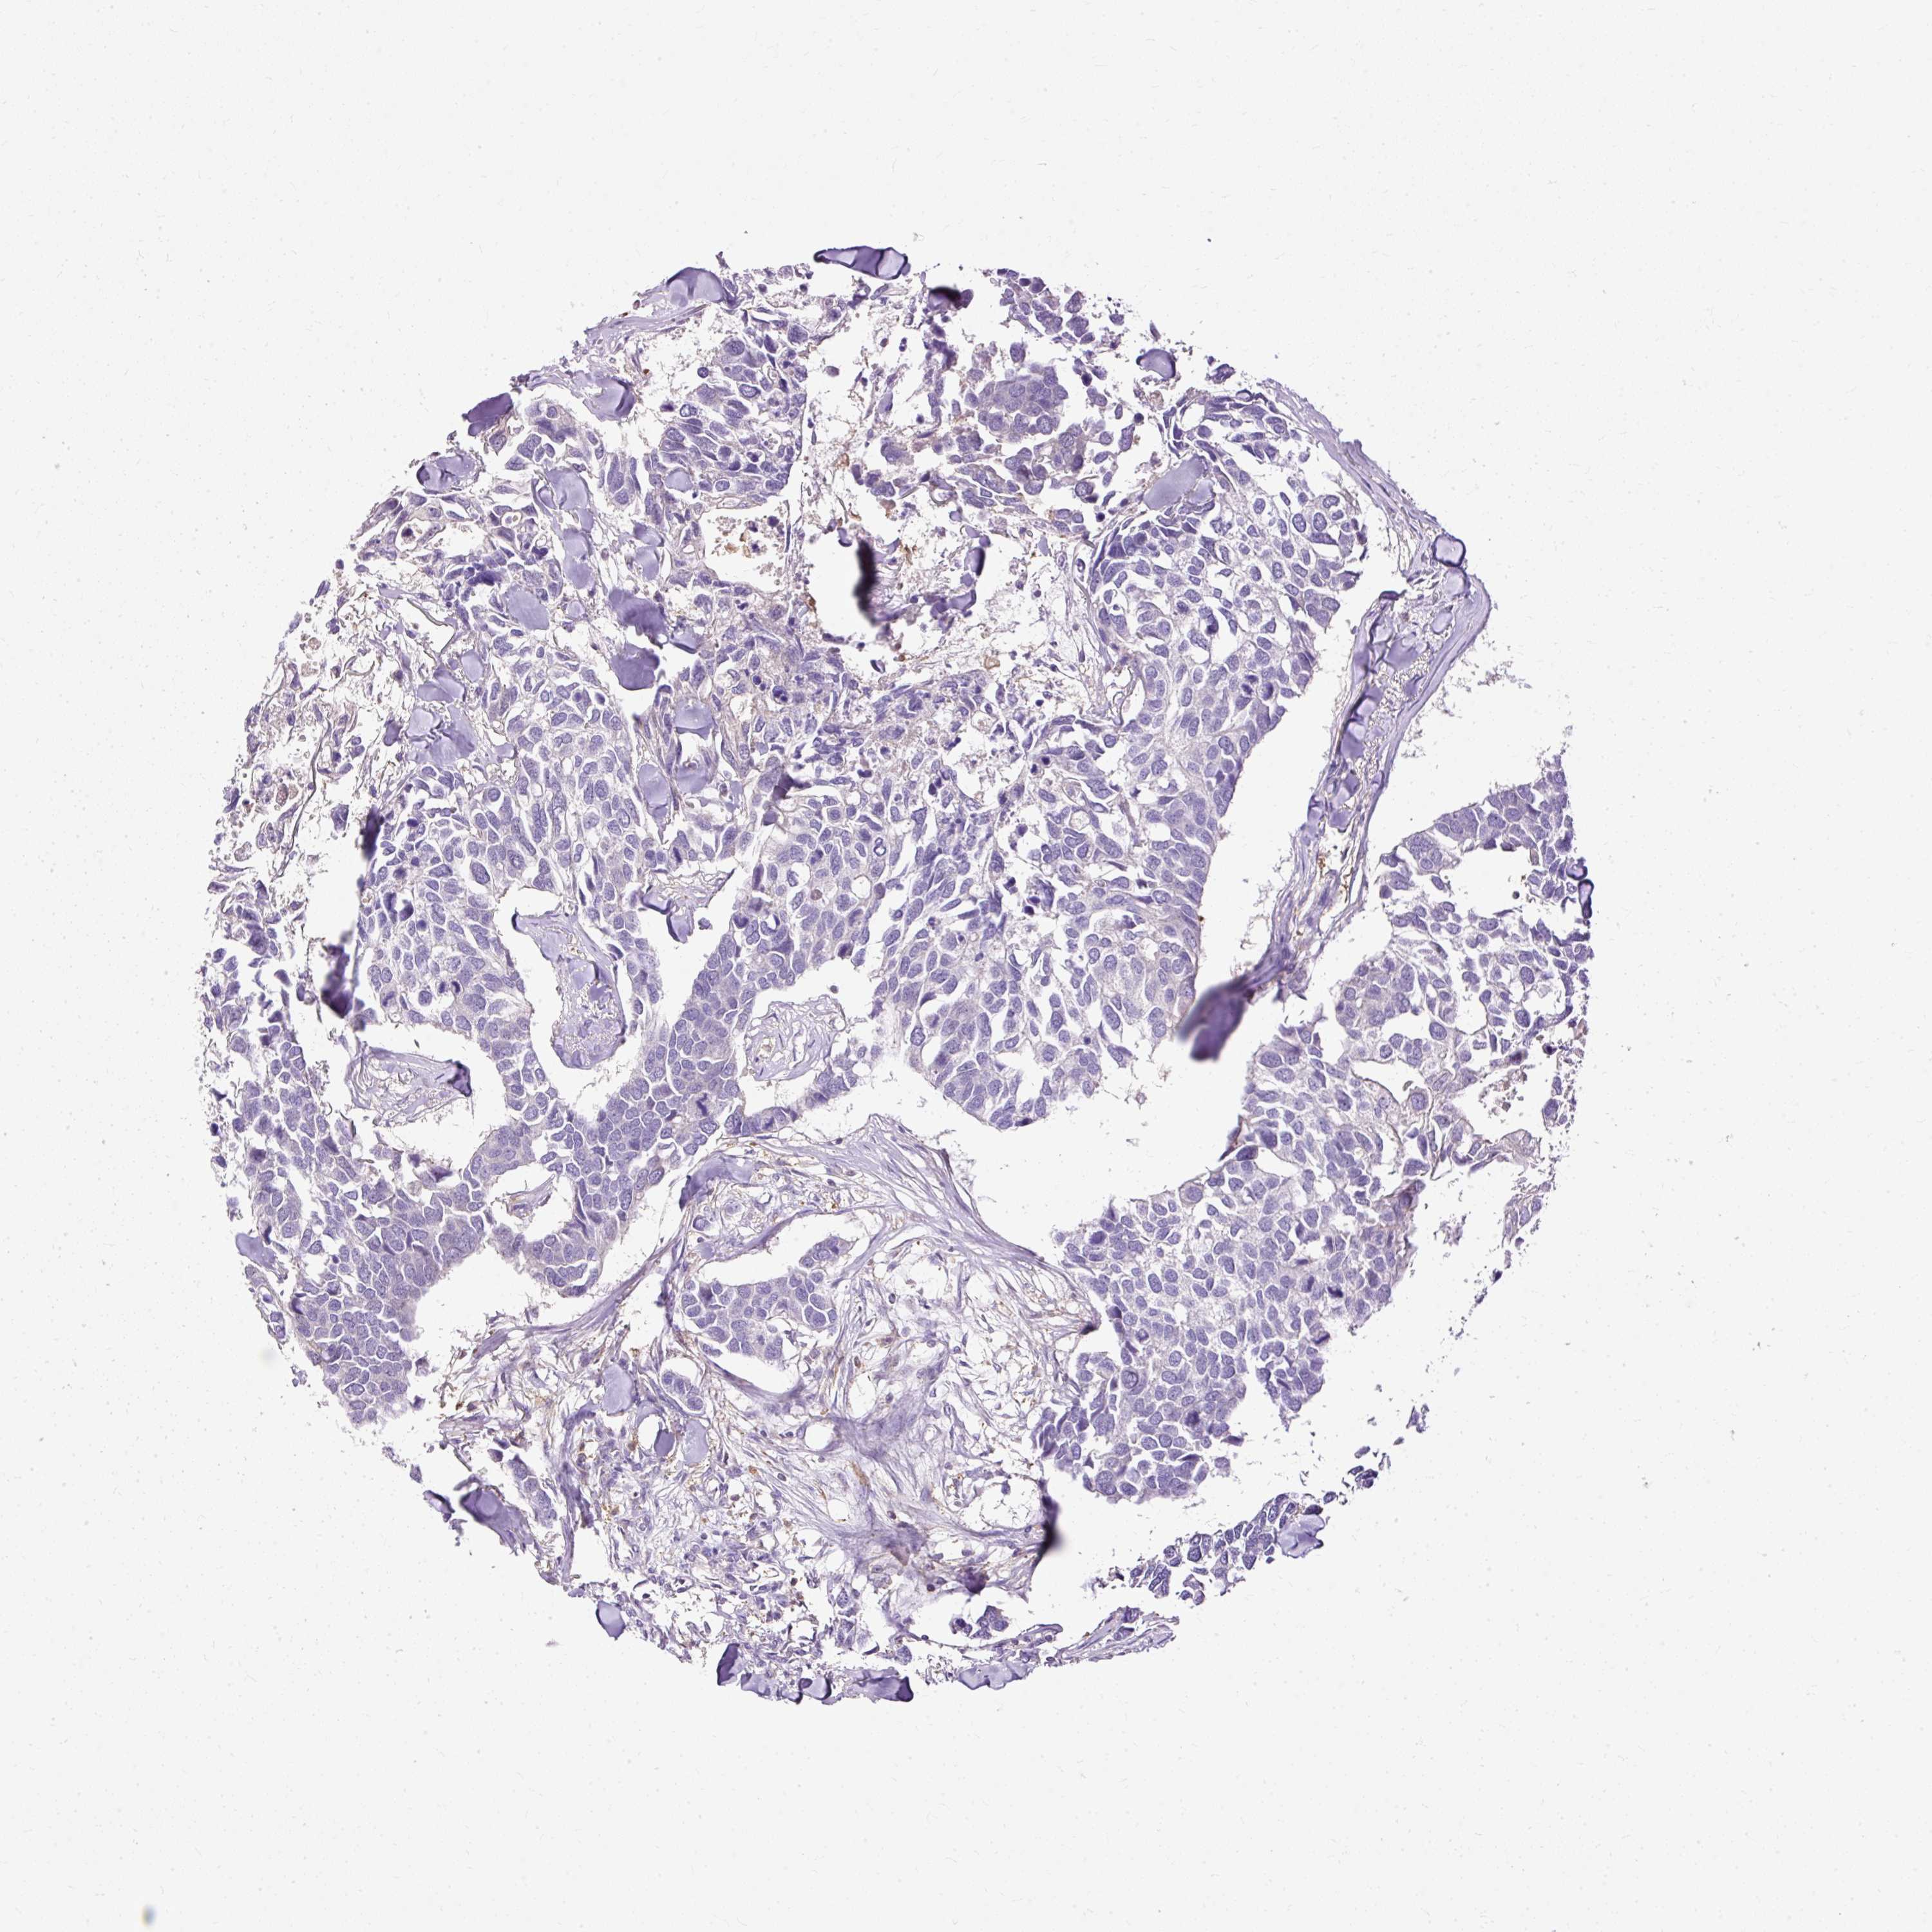

CANCER BREAST CANCER Show tissue menu

Breast cancer

Human cancer